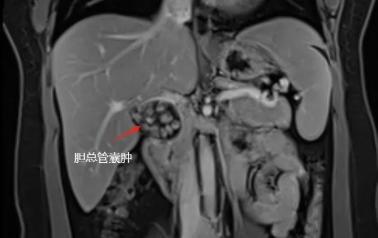

胆总管内有一肿物

且里面装满胆石

最终入院后确诊为先天性胆总管囊肿Ia型,我院肝胆外科卢明柱主任团队为患者提供了详细的治疗方案——微创手术切除畸形扩张的胆管,该手术创伤小,恢复快,疗效确切,单女士欣然接受手术方案,并于近日实施了手术(腹腔镜下胆总管囊肿切除+胆囊切除+肝总管空肠Rou-en-Y吻合)。目前,单女士术后恢复良好,已顺利出院。